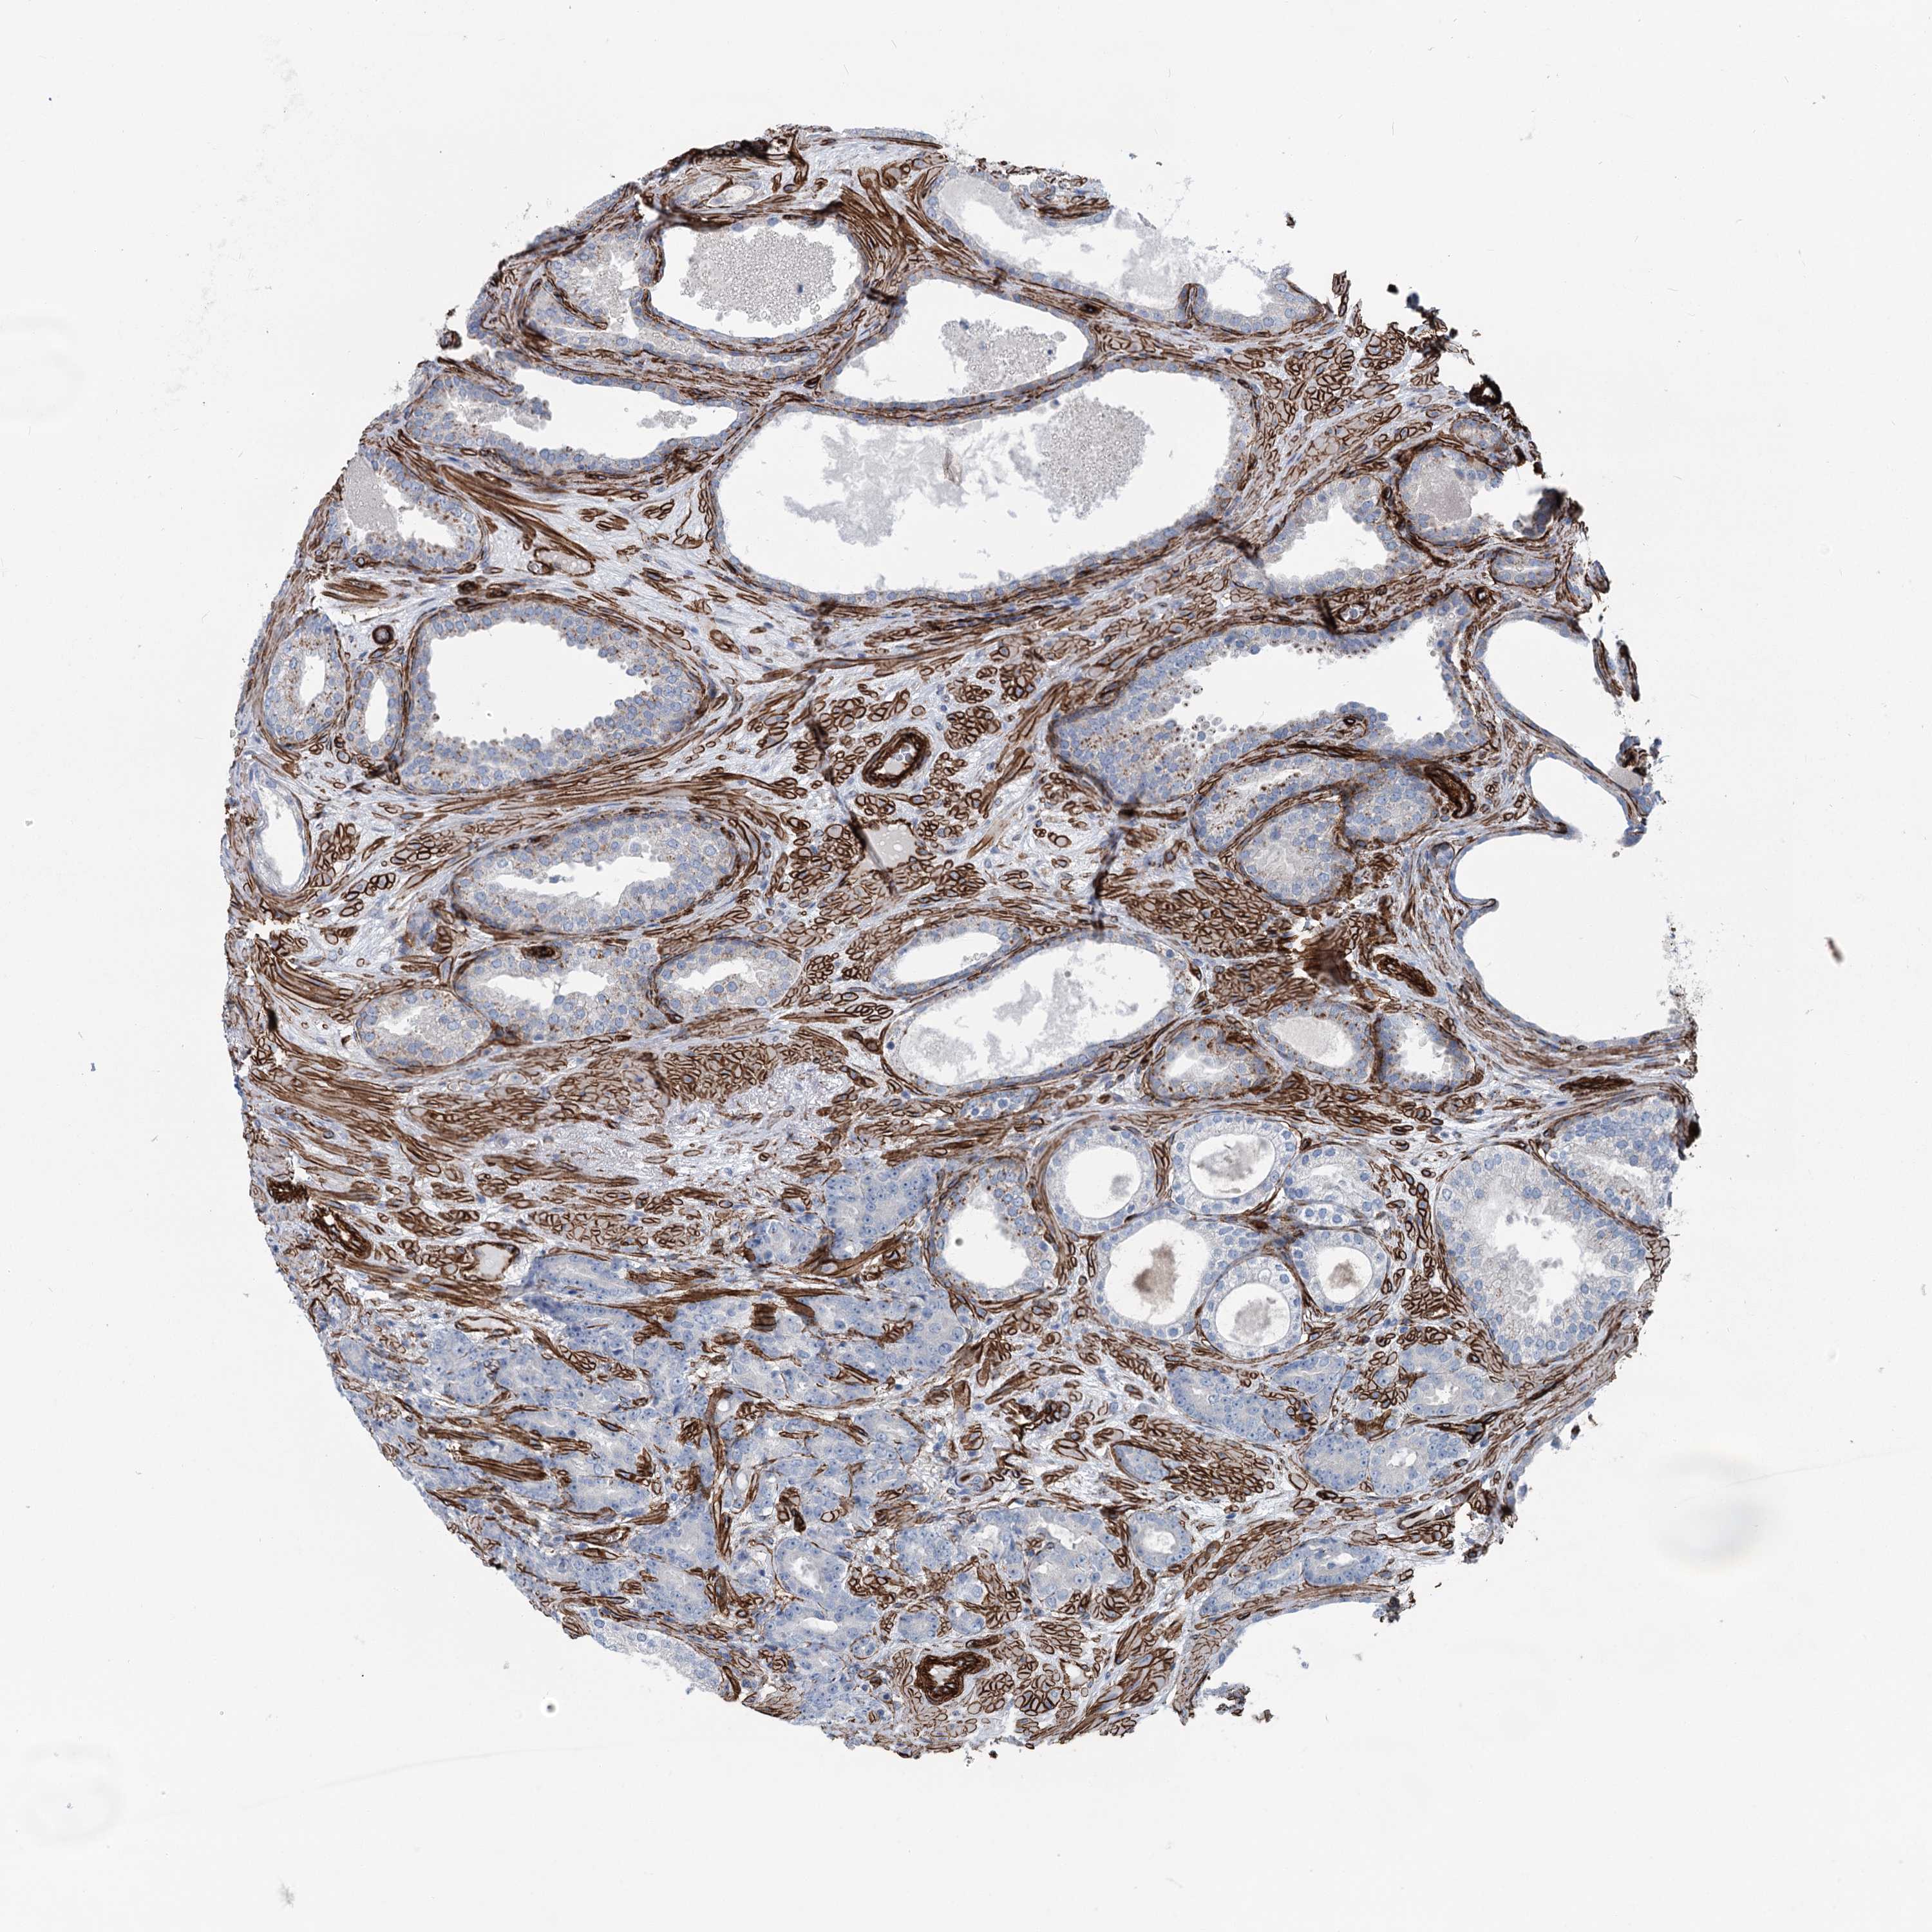

PROSTATE CANCER - Protein expressioni

A mouse-over function shows sample information and annotation data. Click on an image to view it in a full screen mode. Samples can be filtered based on level of antibody staining by selecting one or several of the following categories: high, medium, low and not detected. The assay and annotation is described here.

Antibody stainingi

Antibody staining in the annotated cell types in the current human tissue is reported as not detected, low, medium, or high, based on conventional immunohistochemistry profiling in selected tissues. This score is based on the combination of the staining intensity and fraction of stained cells.

Each image is clickable and will lead to virtual microscopy that enables deeper exploration of all samples and also displays staining intensity scores, fraction scores and subcellular localization as well as patient and tissue information for each sample.

Antibody HPA038143

Antibody HPA038144

Staining

High

Medium

Low

Not detected

Intensity

Strong

Moderate

Weak

Negative

Quantity

>75%

75%-25%

<25%

None

Location

Nuclear

Cytoplasmic/membranous

Cytoplasmic/membranous,nuclear

Adenocarcinoma, NOS

Adenocarcinoma, High grade

Adenocarcinoma, Low grade